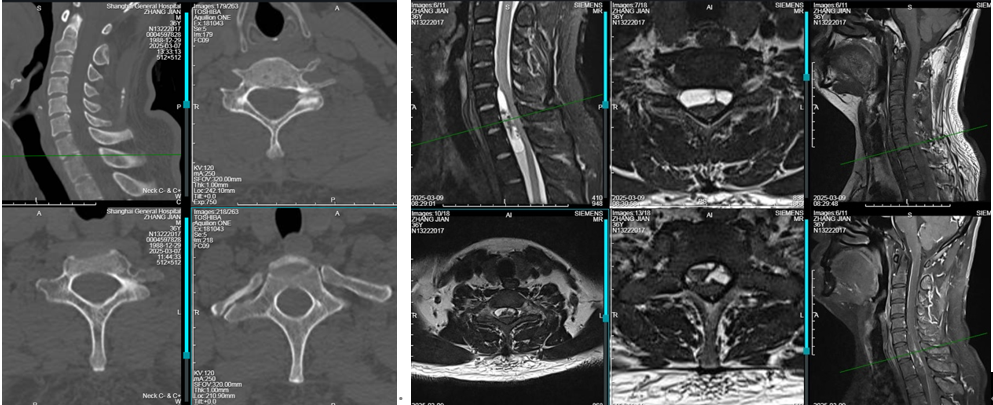

患者男性,36岁,家中主要劳动力,已婚已育。因“颈部僵硬不适,双上臂、背部牵拉疼痛5年余,加重1月”入院。